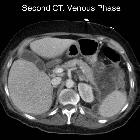

Necrotizing

pancreatitis: peripancreatic necrosis alone. CT is repeated four weeks later. The walls of these collections show an enhancing wall after intravenous contrast administration, which is indicative of walled-off necrosis (WON).